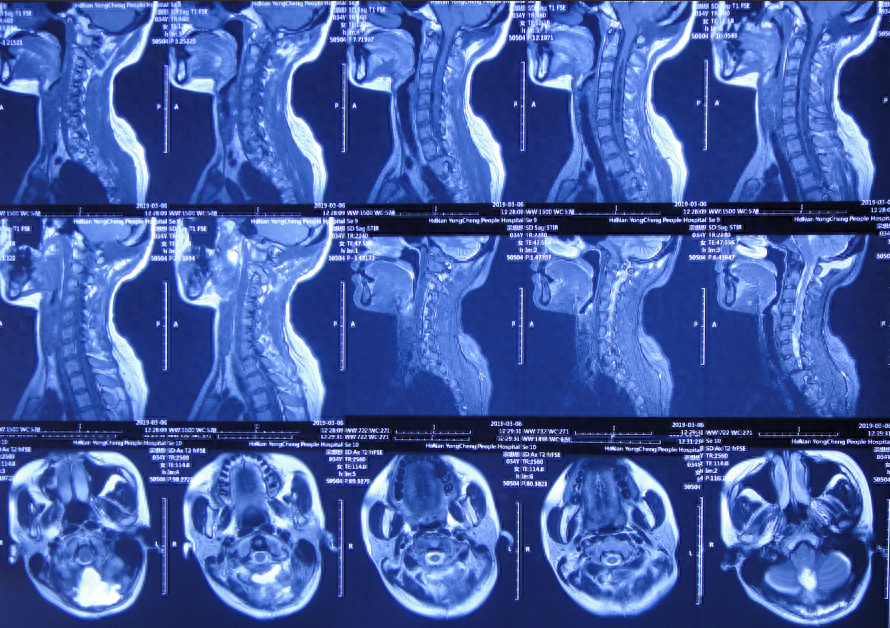

小脑扁桃体下疝减压术后20天即2019年3月6日,查头颅、颈椎核磁发现仍有脊髓空洞(图-8、图-9)。

图-8:2019年3月6日头颅核磁

图-9:2019年3月6日头颅核磁

入院当天头颅CT示小脑扁桃体下疝减压术后,枕下可见低密度影。脑室系统稍扩张(图-12);颈椎核磁脊髓可见空洞形成(片子丢失)。

入院治疗42天即2019年5月9日,头痛和体温均已完全正常近1月,查颈椎核磁示脊髓空洞有变小(图-16)。

图-16:2019年5月9日颈部核磁

出院后8个月即2020年1月9日,来院复查。复查时:身体完全正常(图-19),查颈椎核磁:无异常(图-20)。

图-20:2020年1月9日颈部核磁